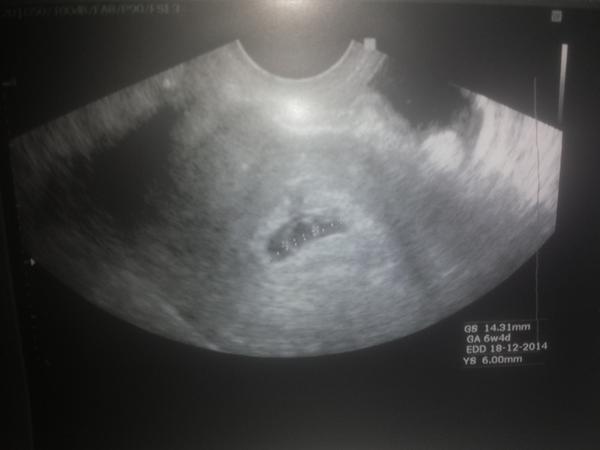

Ahojte baby, chcem vás len povzbudiť, ja budem mať v máji 42 a našla som si včera dve čiarky na teste. Tak dúfam, že budú silnieť. Bolo to plánované a na prvú šupu. Môj problém je prekonať tie prvé tri mesiace. Mám za sebou 3 MA. Ale len s druhým mužom. S prvým mám dve deti, obe na prvý krát a bezproblémové tehotenstvo. No to som mala o dvadsať menej. 😕 Ale nestrácam nádej, máme za sebou rôzne vyšetrenia a nič sa nenašlo. Tak skúšame ďalej. Posledný potrat so mala v januári. Stále to skončí tak medzi 6 - 8 tt.